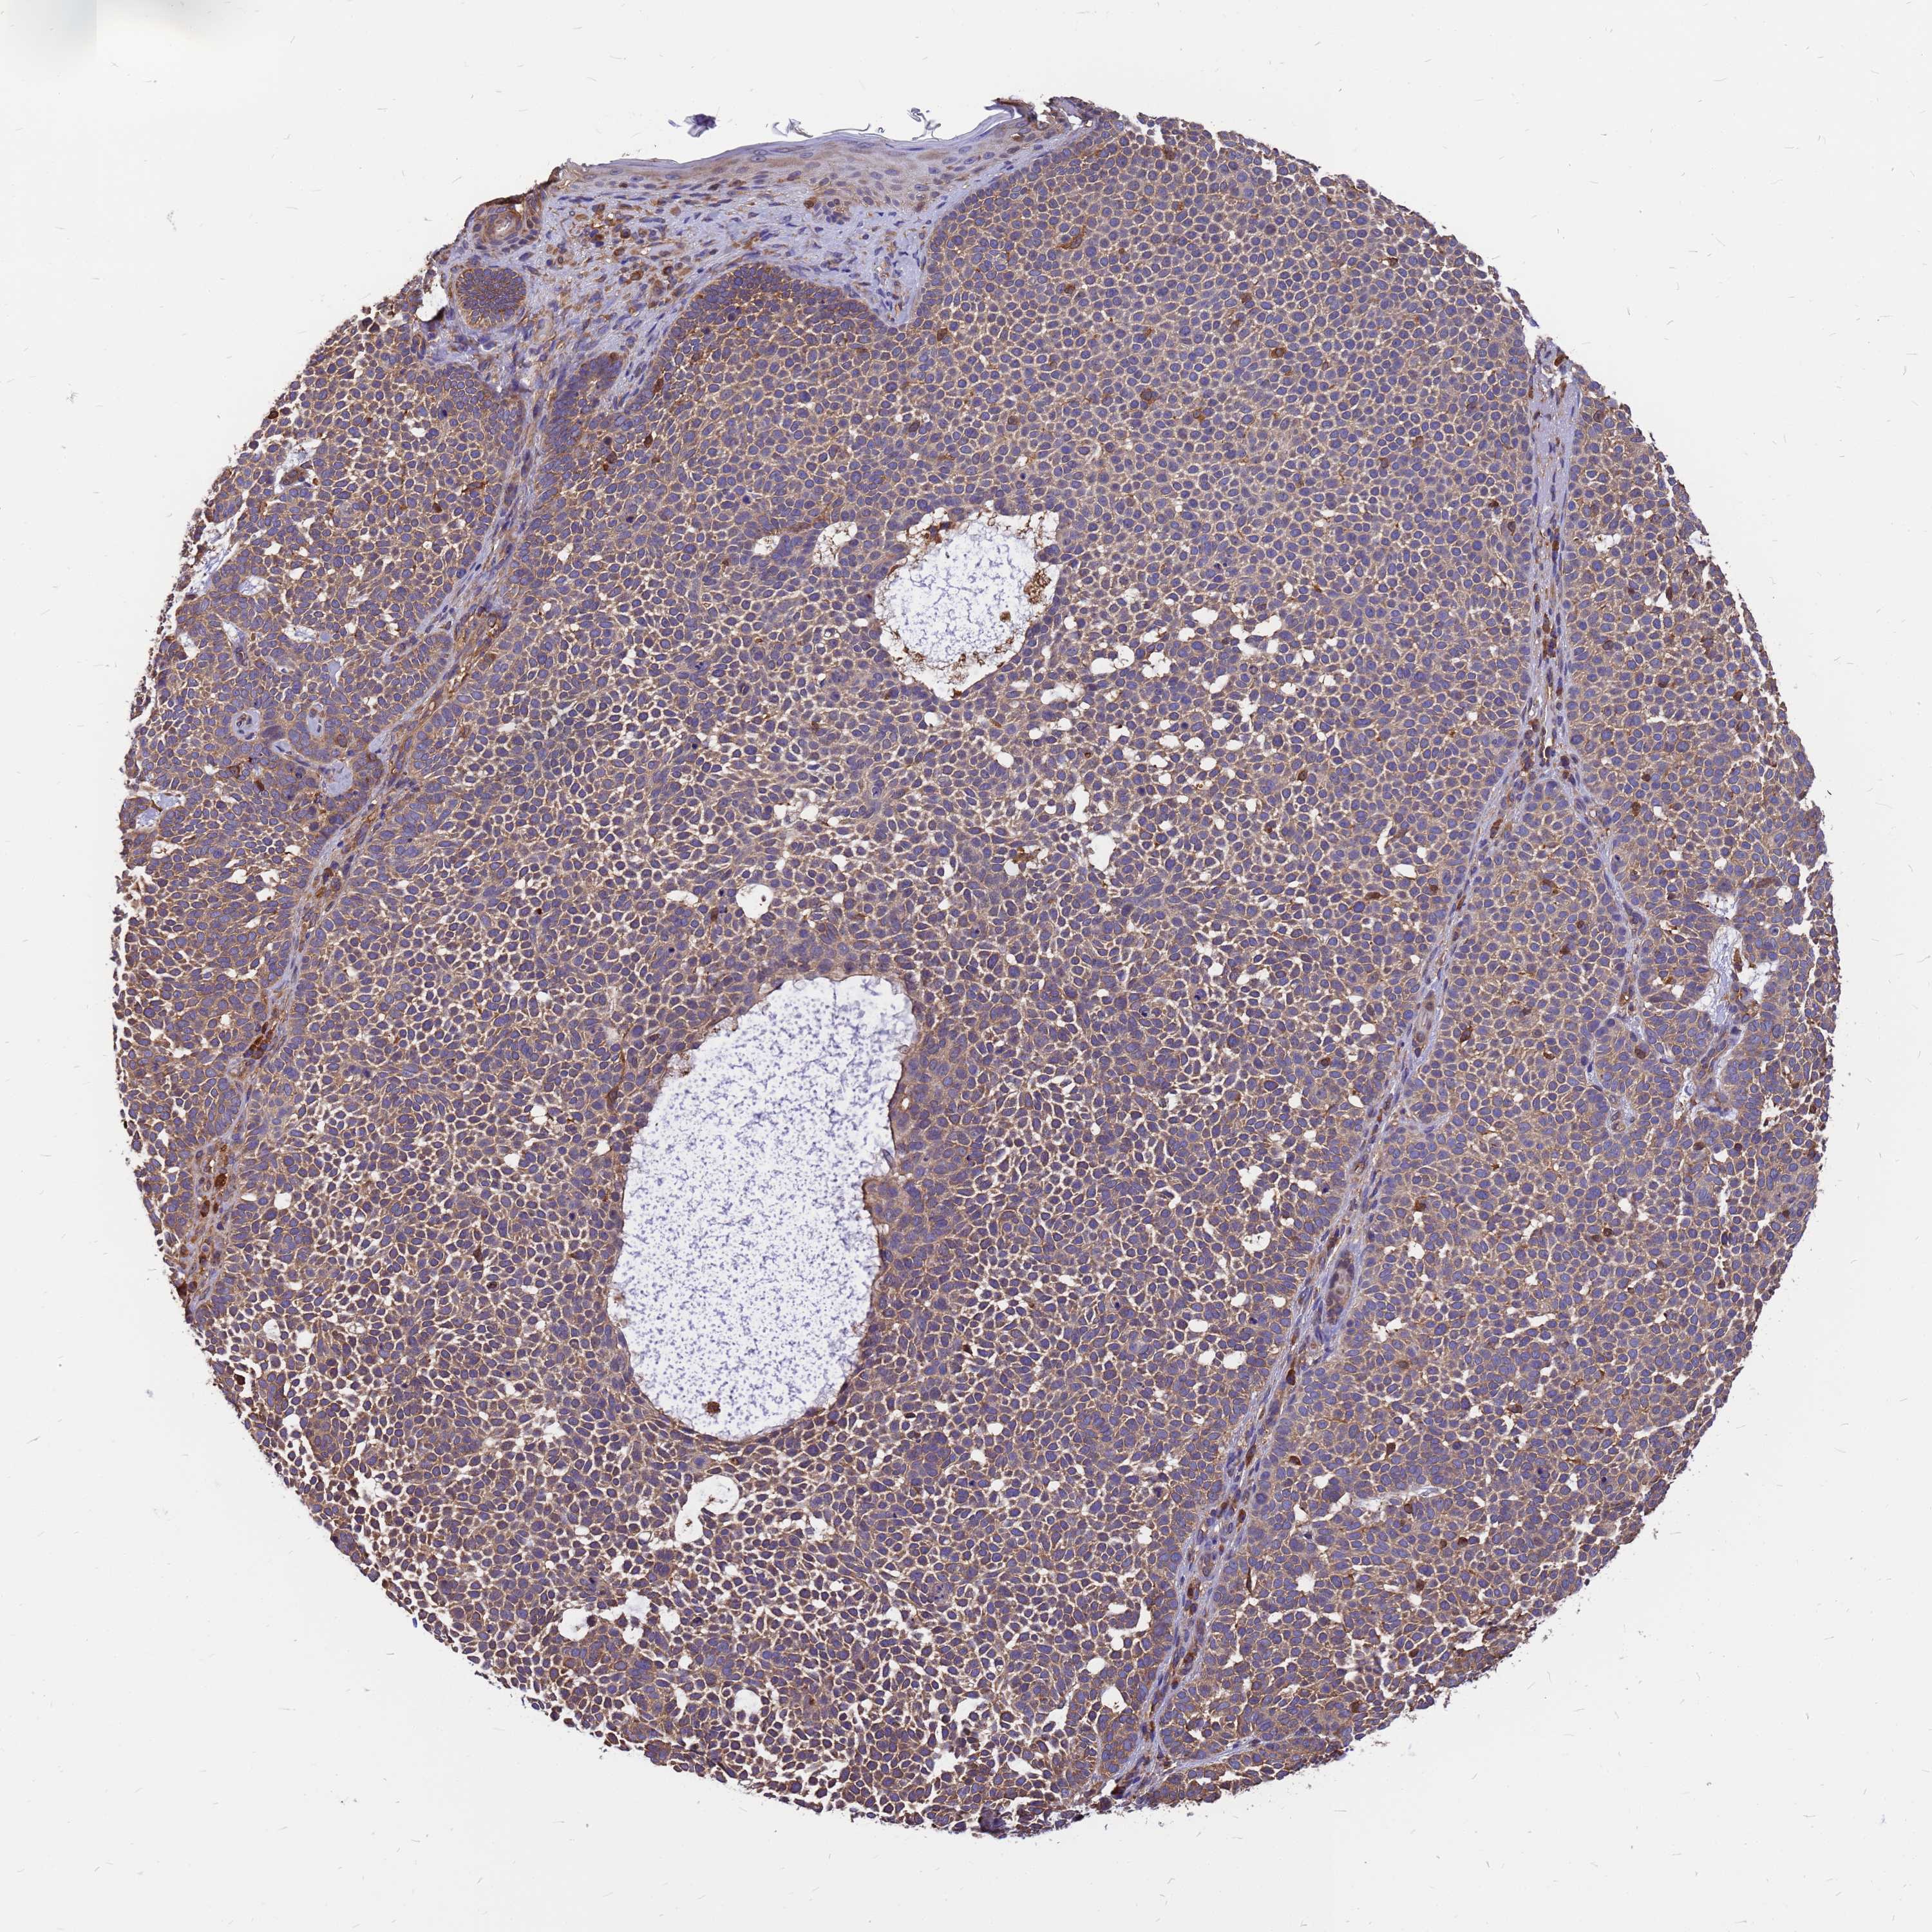

SKIN CANCER - Protein expressioni

A mouse-over function shows sample information and annotation data. Click on an image to view it in a full screen mode. Samples can be filtered based on level of antibody staining by selecting one or several of the following categories: high, medium, low and not detected. The assay and annotation is described here.

Antibody staining in the annotated cell types in the current human tissue is reported as not detected, low, medium, or high, based on conventional immunohistochemistry profiling in selected tissues. This score is based on the combination of the staining intensity and fraction of stained cells.

Each image is clickable and will lead to virtual microscopy that enables deeper exploration of all samples and also displays staining intensity scores, fraction scores and subcellular localization as well as patient and tissue information for each sample.

Antibody HPA044348

Squamous cell carcinoma, NOS